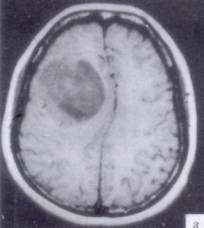

病历摘要:??患者男性,52岁。头痛伴呕吐2月,呕吐呈喷射性。既往身体健康。体检:神清,表情淡漠,反应迟钝,双眼底视神经乳头明显水肿,左鼻唇沟稍浅,左腹壁...

问题 病历摘要:??患者男性,52岁。头痛伴呕吐2月,呕吐呈喷射性。既往身体健康。体检:神清,表情淡漠,反应迟钝,双眼底视神经乳头明显水肿,左鼻唇沟稍浅,左腹壁反射减弱,左上下肢肌力4级,左Babinski征(-)。 下列的术后处理哪些是正确的?